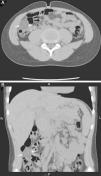

Mediante TC abdominal (fig. 2), se confirma un área focal de aumento de densidad de la grasa intraabdominal adyacente al colon ascendente.

TC abdominal sin contraste por vía oral ni intravenosa, en planos axial (imagen A) y reconstrucción coronal (imagen B). Se observa un área bien delimitada de aumento de densidad de la grasa omental (flechas) del vacío derecho, en situación lateral con respecto al colon ascendente (C) con efecto masa e impronta sobre el mismo, de aspecto trabeculado, con un tamaño de 2,6cm de diámetro.